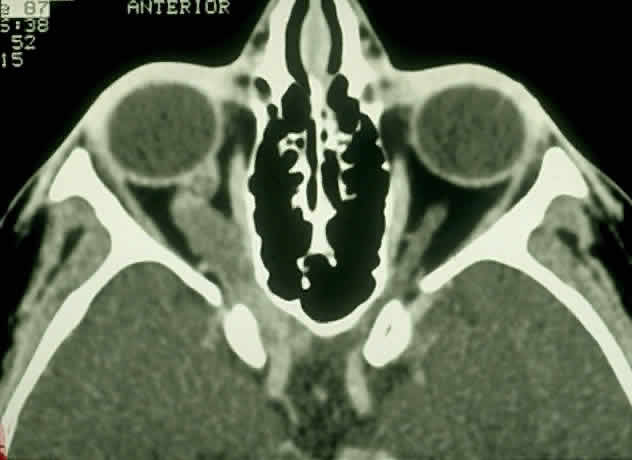

With the availability of computerized tomography (CT) and magnetic resonance imaging (MRI), invasive diagnostic techniques such as arteriography and pneumoencephalography should not be performed in the routine workup of presumed optic gliomas.71 CT scanning may demonstrate enlargement of the optic nerve or chiasm by a glioma (Fig. 3). Because optic gliomas typically appear isodense to normal brain,72 and because the degree of contrast enhancement ranges from imperceptible to moderate on CT imaging,73 the margins of the tumor may not be well delineated. Optic gliomas usually have a well-outlined fusiform shape, which may include kinking or buckling of the optic nerve. Chiasmal tumor appearance may range from a tubular thickening of both optic nerves and chiasm to massive, multilobular growths.74 Cystic spaces representing mucinous accumulation have been described. These cysts may enlarge and damage adjacent structures, requiring surgical intervention.74,75 Calcific change has also been documented in gliomas, but it is a rare radiologic finding.13 In following patients clinically, it is important to understand that radiologic progression of optic gliomas on CT scans may not correlate clinically with worsening visual function. Conversely, a decline or improvement in visual status may occur despite a lack of corresponding changes on neuroimaging.73,76

Fig. 3. Contrast-enhanced axial CT scan showing an enlarged, kinked optic nerve with posterior extension of the glioma through the optic canal. Note the widening of the optic canal on the right. (Courtesy of Orlando Ortiz, MD, and Jeffrey Hogg, MD)